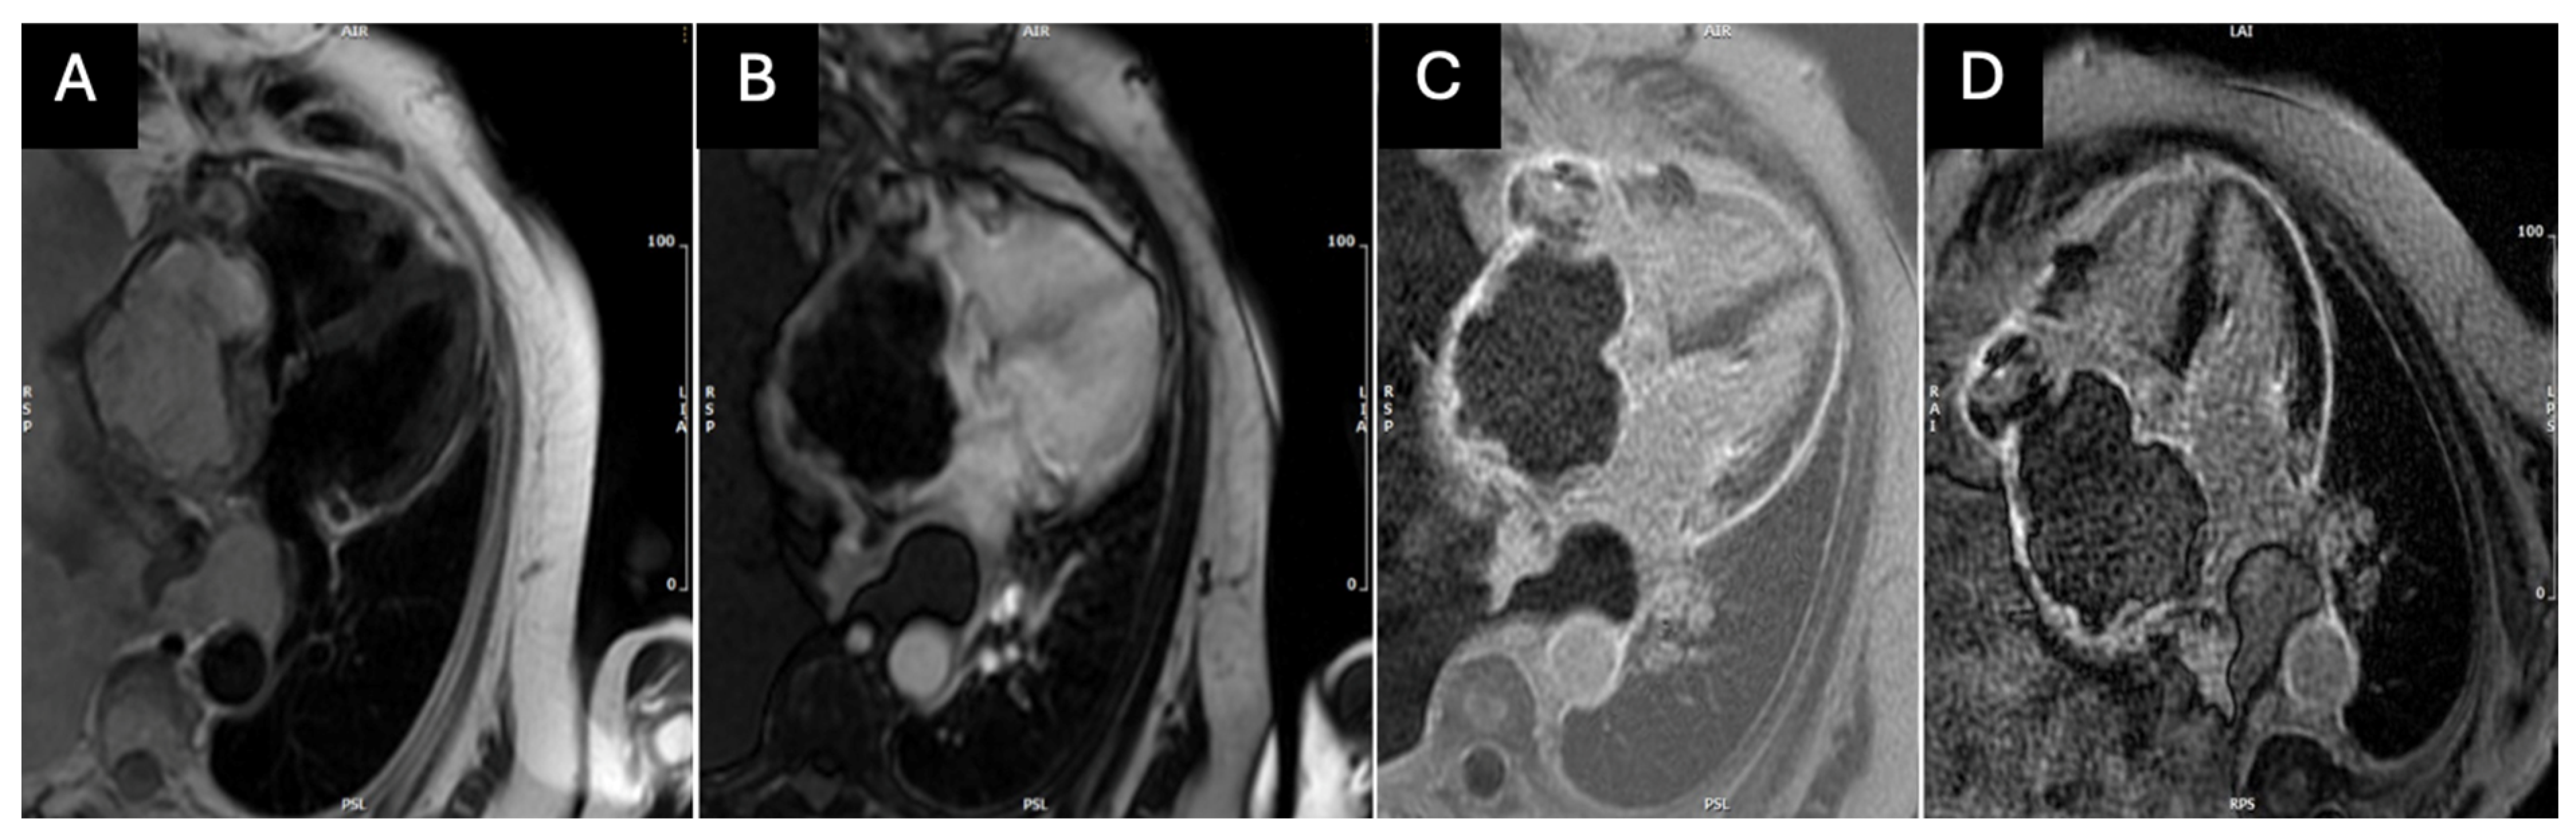

2. Case Presentation